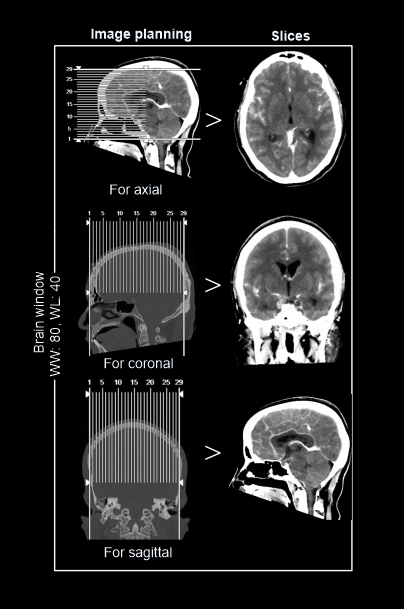

Post-processing

- 5 mm axial images in brain window (WW80, WL40) of both pre and post contrast images.

- 1-2mm axial, coronal or sagittal images of the skull in bone window (WW3500, WL350) to show fractures, dislocations or bony abnormalities.